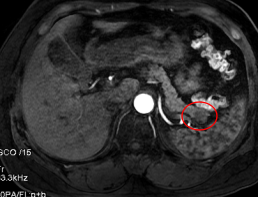

经过磁共振检查后仔细阅片,放射科医生发现张阿姨的胰腺尾部的确是长了一个类圆形的小肿瘤。

磁共振片

张阿姨随后转到肝胆胰外科进行腹腔镜下病灶切除手术,术中在胰腺尾部切除一个直径约2.5cm大小的肿瘤,术后的病理报告证实是胰岛素瘤(一种功能性胰岛细胞瘤)。